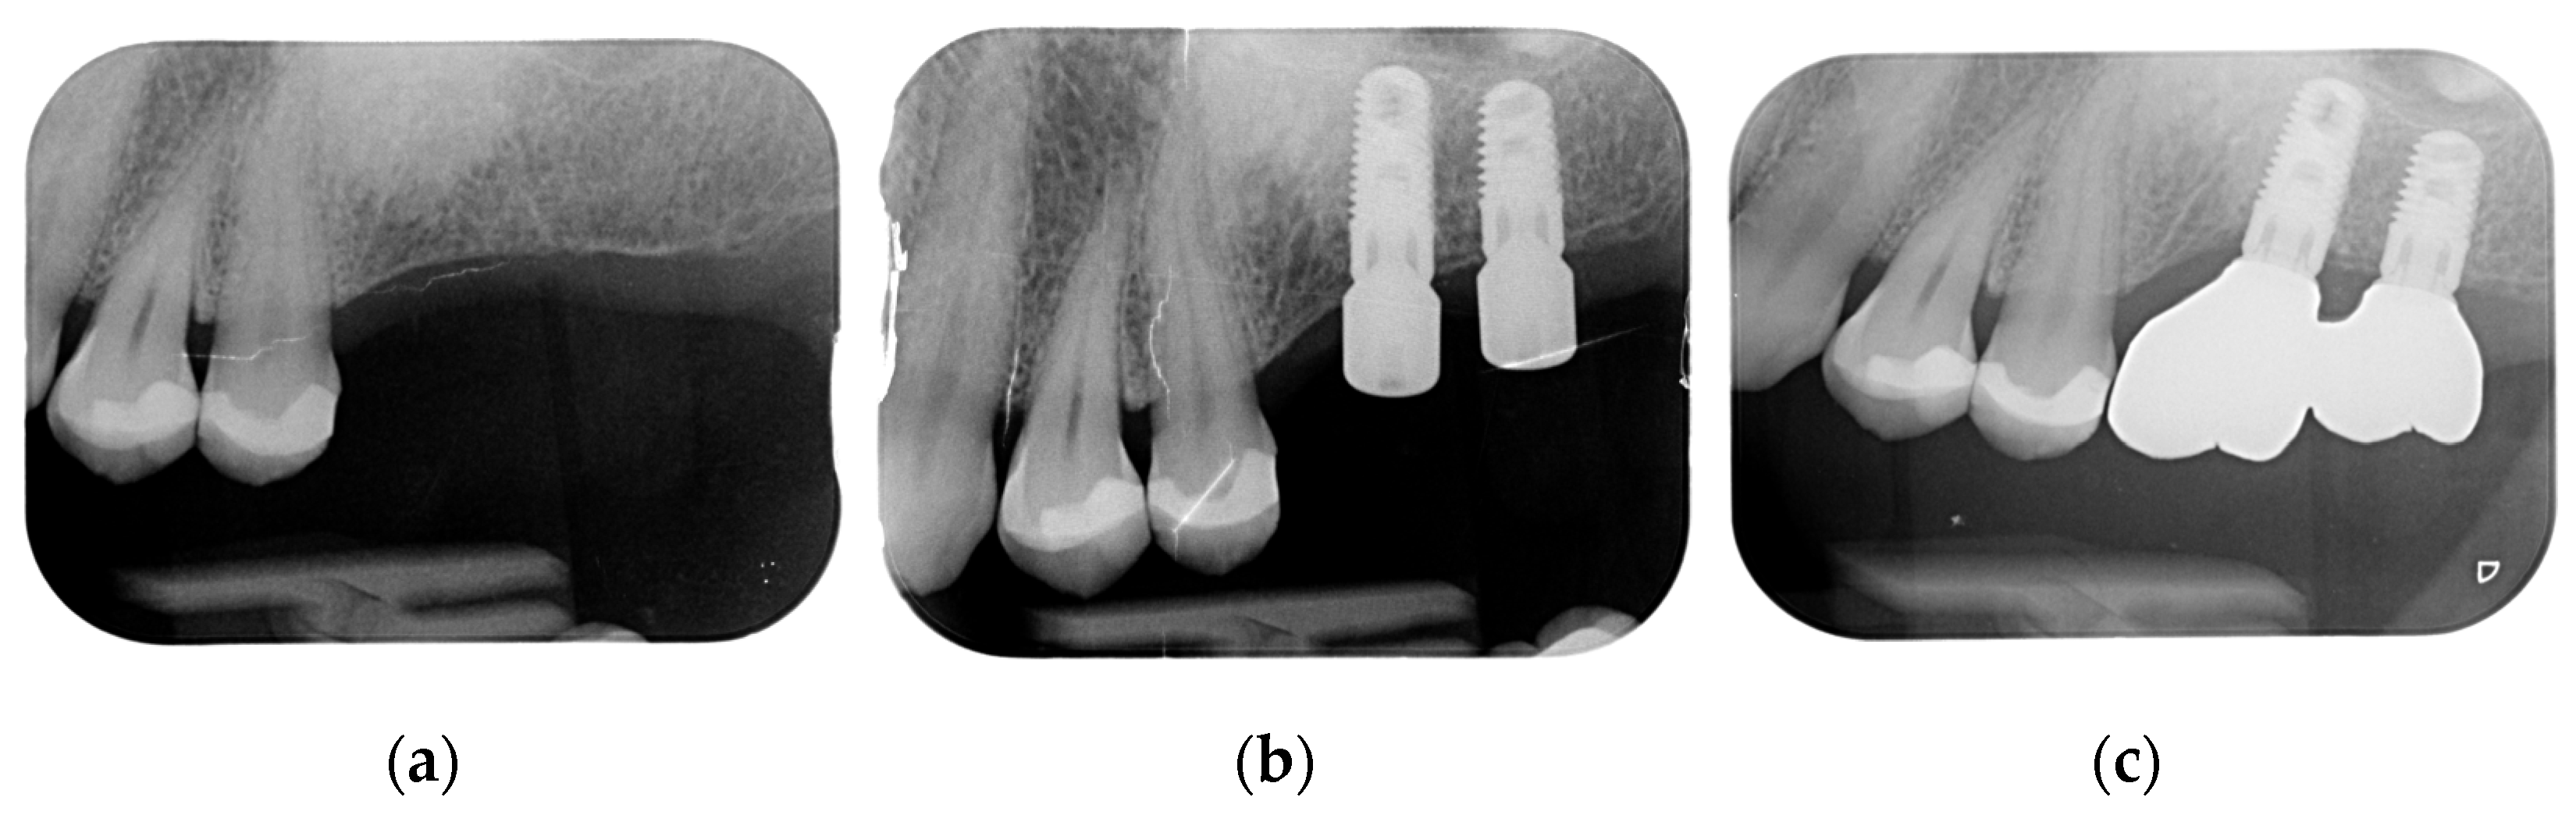

Implant rehabilitation was suggested. For this, a panoramic X-ray was performed, and it showed a homogeneous radiopacity in the left upper jaw, with feathered edges of about 10 mm in dimension (Figure 2).

Figure 2.

Orthopanoramic X-ray showing radiopacity in left upper jaw.

Juxta-gingival view of the surgical site: (a) preoperative view; (b) implants’ placement; (c) prosthetic on implants.

Figure 10.

Crowns on implants.